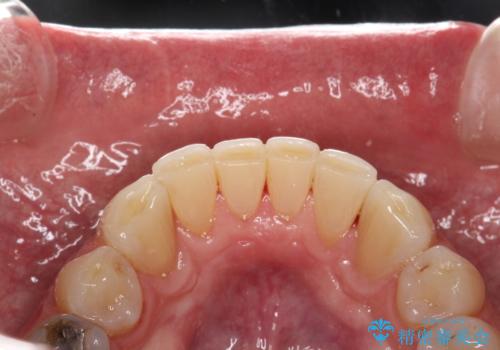

- 歯と歯の間の歯石が気になるとのことで来院されました。PMTC30分コースを行いました。プラークコントロールも悪かったため、歯ブラシ指導も行いました。

プラークが放置されると、そこで病原菌が繁殖し始めます。そうなるとバイオフィルム(歯面に強固に付着したばい菌の膜)になり、歯肉に炎症が生じ歯周病の引き金となります。

プラークやバイオフィルムといった細菌などを放置すると歯石となります。歯石になってしまうと歯磨きでは取り除くことができないため、歯科医院にて専門的な機械や材料を使用してクリーニングを受ける必要があります。